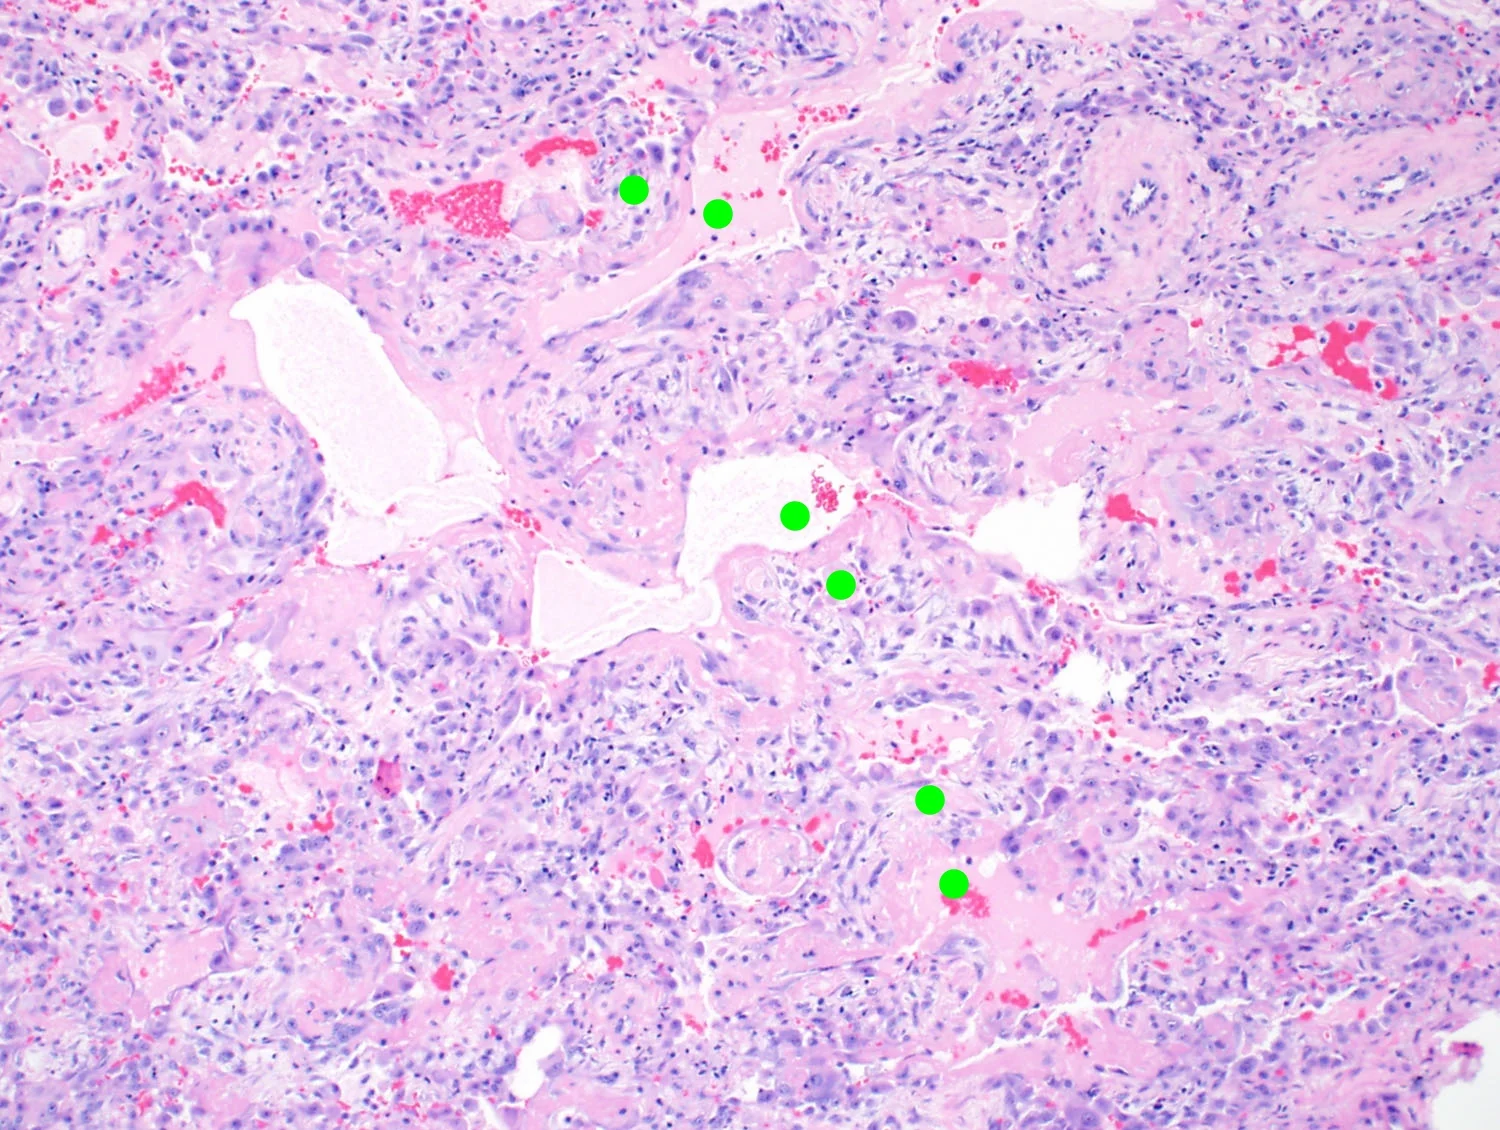

Organizing Pneumonia

Polyps of immature fibroblastic tissue proliferating in the airspaces. What's the difference between OP and fibroblast foci?

Fibrin

Globules of densely eosinophilic material in the airspaces.